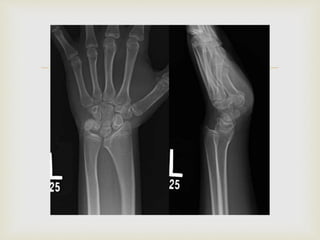

 The radius is curved, with its convexity dorsal and radial,

and there is a similar angulation of the distal radial

articular surface. The forearm is relatively short.

 The distal radial epiphysis is triangular because of the

failure of growth in the ulnar and volar aspects of the

physis; early closure of these aspects of the physis also is

frequent.

 The ulna is subluxated dorsally, the ulnar head is

enlarged, and the overall length of the ulna is decreased.

 The carpus appears to have subluxated ulnarward and

palmarward into the distal radioulnar joint, which

usually is spread apart.

 The carpus appears wedge shaped, with its apex proximal

within the lunate.

  The radiusis curved, with its convexity dorsal and radial, and there is a similar angulation of the distal radial articular surface. The forearm is relatively short.  The distal radial epiphysis is triangular because of the failure of growth in the ulnar and volar aspects of the physis; early closure of these aspects of the physis also is frequent.  The ulna is subluxated dorsally, the ulnar head is enlarged, and the overall length of the ulna is decreased.  The carpus appears to have subluxated ulnarward and palmarward into the distal radioulnar joint, which usually is spread apart.  The carpus appears wedge shaped, with its apex proximal within the lunate. Radiography